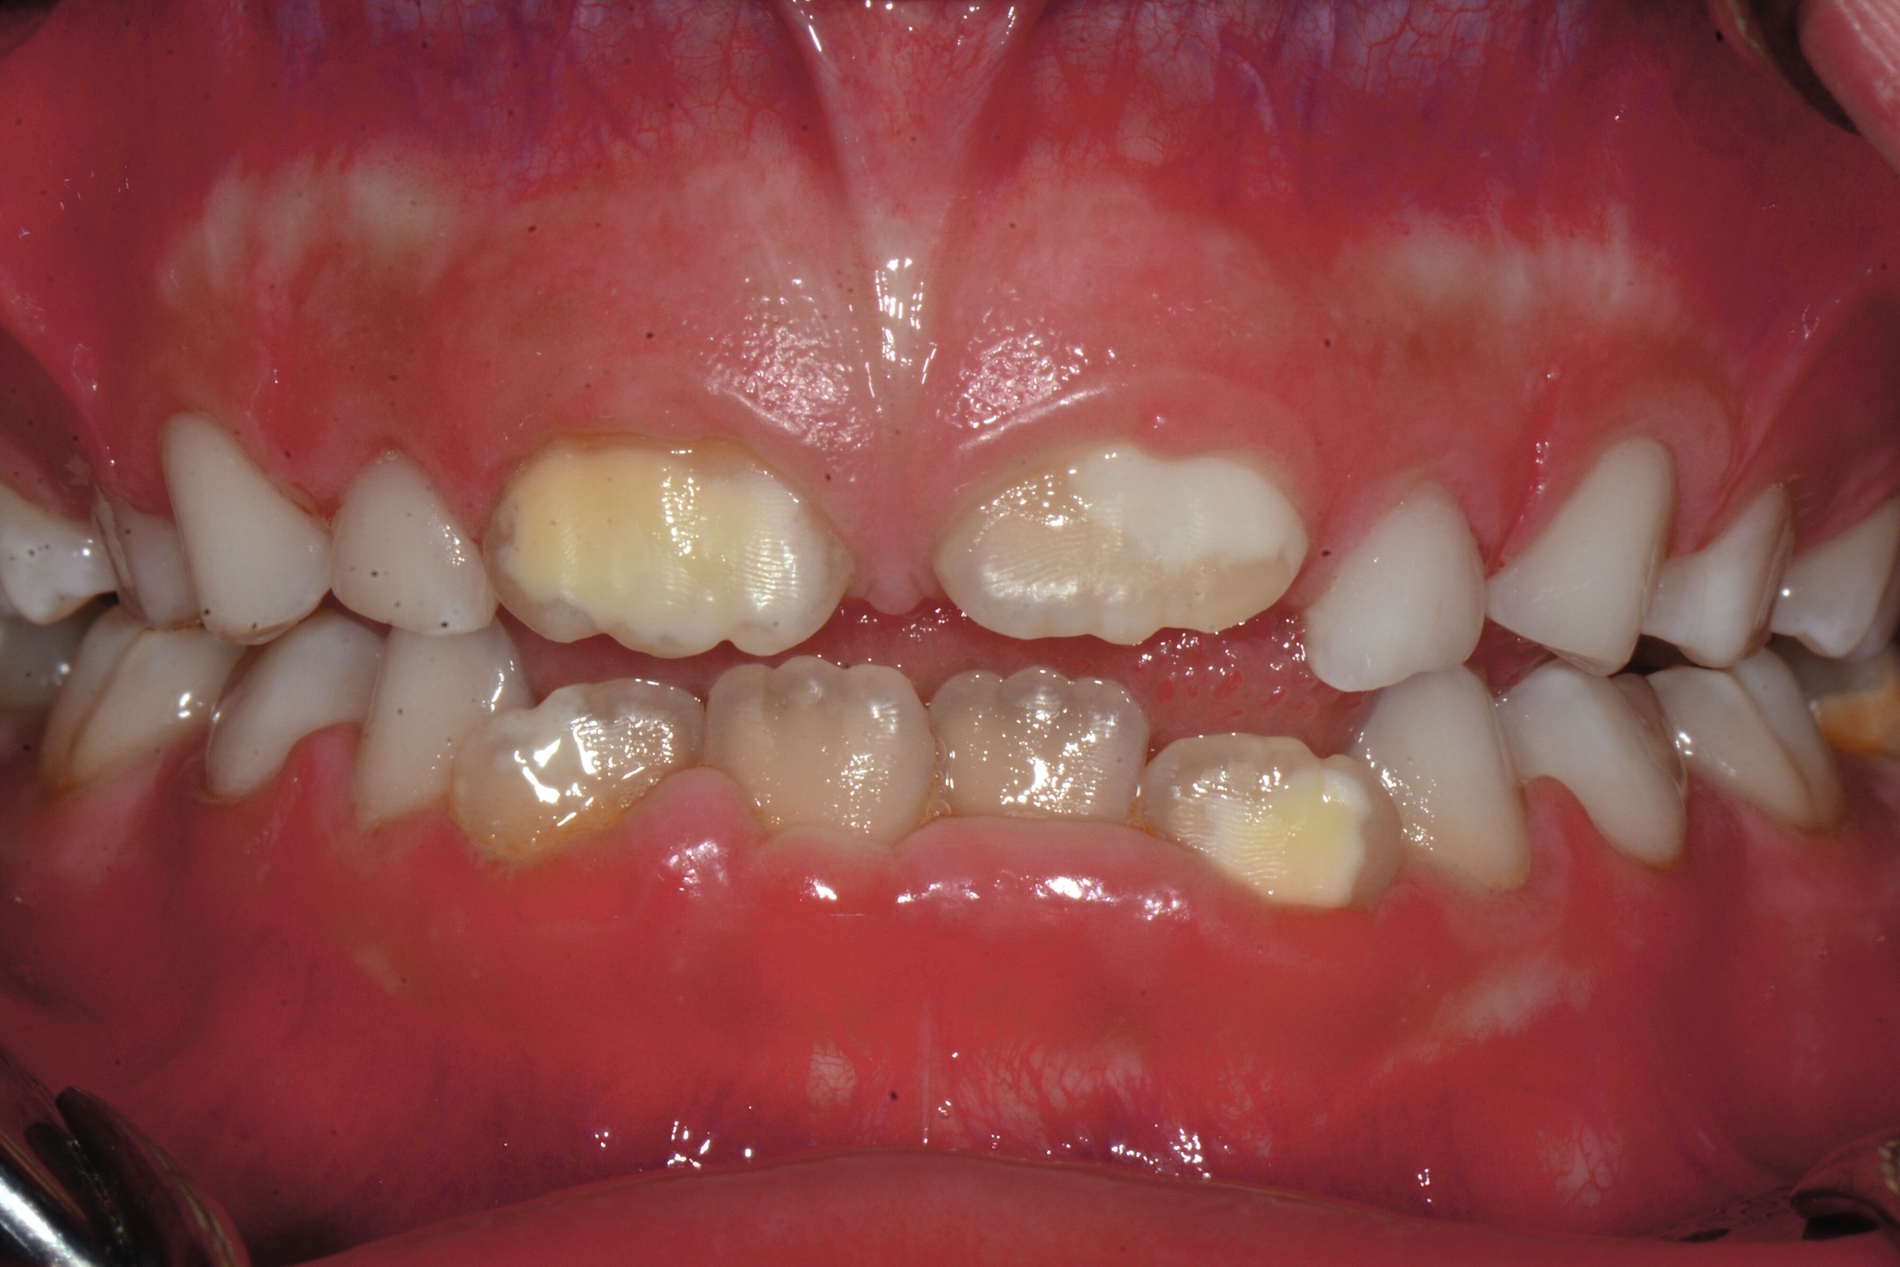

Das klinische Erscheinungsbild an bleibenden Zähnen zeigt typischerweise weißlich-gelbe bis gelblich-braune Opazitäten, die zumindest in einigen Bereichen durch eine scharfe Abgrenzung (engl.:„demarcated opacities“) zum gesunden Zahnschmelz charakterisiert sind (Abbildungen 3 und 4). Die abgegrenzten Hypomineralisationen befinden sich mehrheitlich im Bereich der inzisalen Kronenhälfte unabhängig von dem Auftreten an Front- oder Seitenzähnen. Die Ausprägung am Zahn kann dabei auf einzelne Areale oder Höcker begrenzt sein.

Bei einer schwerwiegenderen Ausprägung sind Zahnflächen vollständig betroffen, mitunter alle Zahnflächen an einem Zahn. Die Verteilung in der Dentition beziehungsweise an den Indexzähnen ist gleichermaßen variabel und betrifft nicht nur die Defektgröße, sondern auch die Farbe und Festigkeit. Was die Festigkeit betrifft, gilt als die Faustregel: Je dunkler die Farbe des Schmelzes, umso weicher beziehungsweise poröser und damit minderwertiger wird dessen Qualität sein. Damit reduziert sich seine kaufunktionelle Belastungsfähigkeit, was insbesondere an ersten bleibenden Molaren von klinischer Relevanz ist.

MIH-typische Befunde finden sich aber nicht nur an ersten bleibenden Molaren oder bleibenden Frontzähnen, sondern prinzipiell an allen Zähnen im bleibenden Gebiss als auch in der Milchzahndentition. Da Hypomineralisationen im Milchgebiss vornehmlich an den zweiten Milchmolaren festzustellen sind, werden diese als Milchmolaren-Hypomineralisation (MMH), Decidous-Molar-Hypomineralisation (DMH) oder Second-Primary-Molar-Hypomineralisation (SPMH) bezeichnet. Obwohl die Namenswahl darauf hindeutet, dass es sich um eine eigene Erkrankungsgruppe handelt, ist davon auszugehen, dass diese Krankheitsbilder zum Formenkreis der MIH gehören.

Eine weitere Strukturstörung ist die Dentalfluorose. Das klinische Erscheinungsbild von Fluorosen unterscheidet sich durch diffuse Opazitäten grundlegend im Vergleich zu den scharf begrenzten Opazitäten der MIH-Zähne. Fluorosen treten symmetrisch und möglicherweise an allen Zähnen infolge einer langfristigen Fluoridüberdosierung auf. Genetisch bedingte Erkrankungen der Zähne, wie Amelogenesis imperfecta und Dentinogenesis imperfecta, werden durch spezifische Genmutationen verursacht und sind dadurch gekennzeichnet, dass alle Zähne beider Dentitionen gleichermaßen betroffen sind [Kühnisch et al., 2025; DGKIZ et al., 2024]. Im Gegensatz dazu sind MIH-Defekte mehrheitlich an den sogenannten Indexzähnen zu finden. Zudem ist oftmals ein symmetrisches Auftreten zu beobachten.